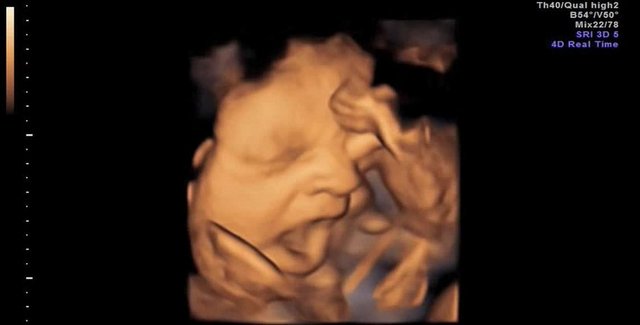

Ultrason çocuk için zararlı mı?Ultrason, görsel şov gibi algılanmamalı, kapsamlı 3 muayene normal olduğu gibi, doktor isterse fazladan olabilir.